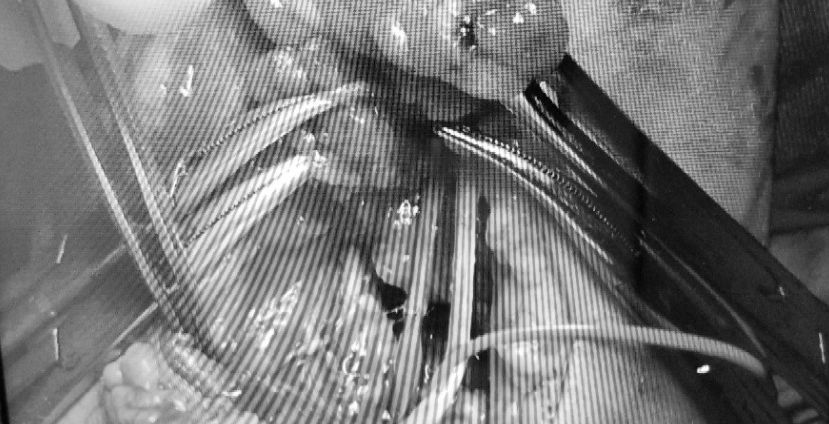

| Bác sĩ tiến hành mổ khẩn cấp cho bệnh nhi |

Qua kiểm tra, bác sĩ nhận thấy bệnh nhi có máu tụ dưới màng cứng, xuất huyết vùng hố sau, dập gan, xương cánh tay gãy hở độ 3, tổn thương động mạch cánh tay trái.

Ê-kíp trực hội chẩn khẩn cấp và quyết định xử trí phẫu thuật ngay. Lúc 0h, bé được đưa vào phòng mổ để kết hợp xương, vi phẫu thuật nối động mạch cánh tay.

Trực tiếp thực hiện nối mạch cho bệnh nhi - BS Nguyễn Thị Ngọc Ngà, Bệnh viện Nhi đồng 2 cho hay, bé bị đa tổn thương nặng, men gan tăng cao, nguy cơ nhiễm trùng, thiếu máu, gây ảnh hưởng tới tính mạng.

Cũng theo BS Ngà, mạch máu bệnh nhi bị dập, có nguy cơ tắc lại cao và cần cân nhắc vấn đề kháng đông, vì thế kíp mổ đứng trước áp lực phải tiến hành nhanh, đúng, chính xác, hạn chế phải mổ lại vì không thể gây mê nhiều lần.

Ca mổ kéo dài 1 giờ thành công trong sự vui mừng từ kíp bác sĩ. Bé sau đó được chuyển qua khoa hồi sức để theo dõi, điều trị bảo tồn các tổn thương ở vùng đầu, gan.